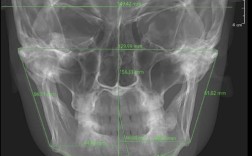

- 拍摄X光片(全景片、头颅侧位片、根尖片等)精确评估牙齿位置、牙根情况、骨量、颌骨关系。

上颌骨发育不足(上颌后缩)或下颌骨发育过度(下颌前突),可能导致牙弓空间相对不足,牙齿拥挤,增加重叠风险。